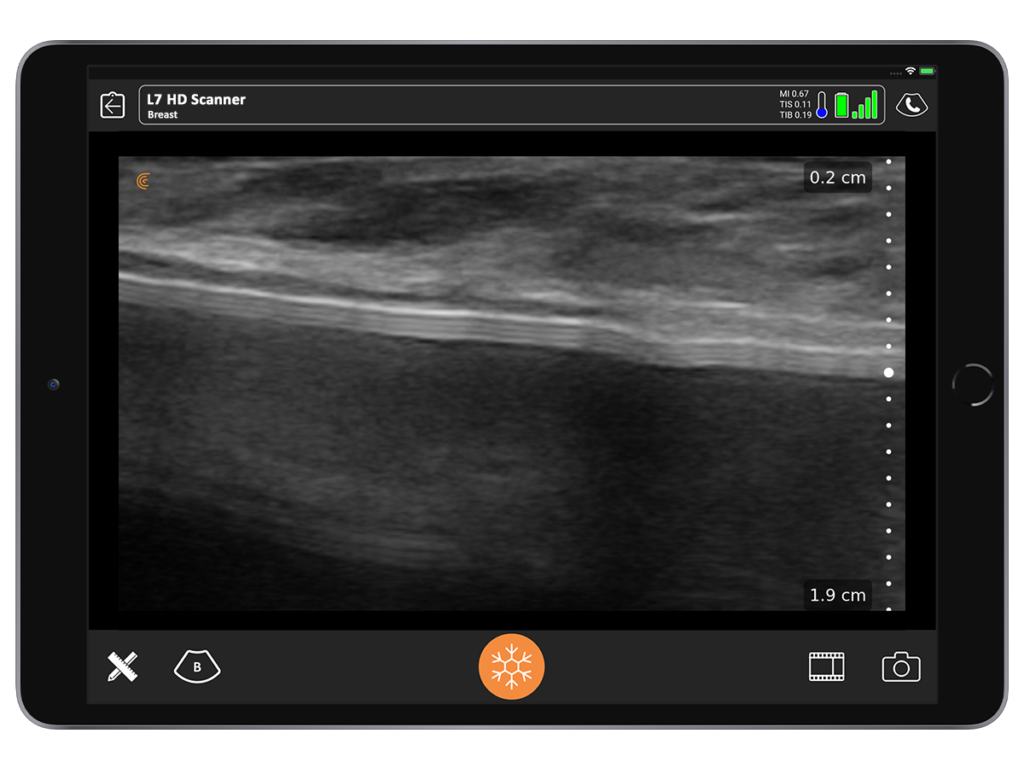

With ultrasound, you can tell a saline implant from a gel implant. You’re also able to differentiate between a textured versus a smooth implant. It’s also very easy to see a seroma. So, if you detect a smooth implant and the absence of seroma, you can tell your patient she’s unlikely to have ALCL.

I often see patients who have been in an accident and feel that something has changed with their implant. It looks and feels different to them and they are concerned that it may be broken.

By performing a quick scan during the consult, I give them immediate peace of mind by confirming with confidence that the implant is not broken.